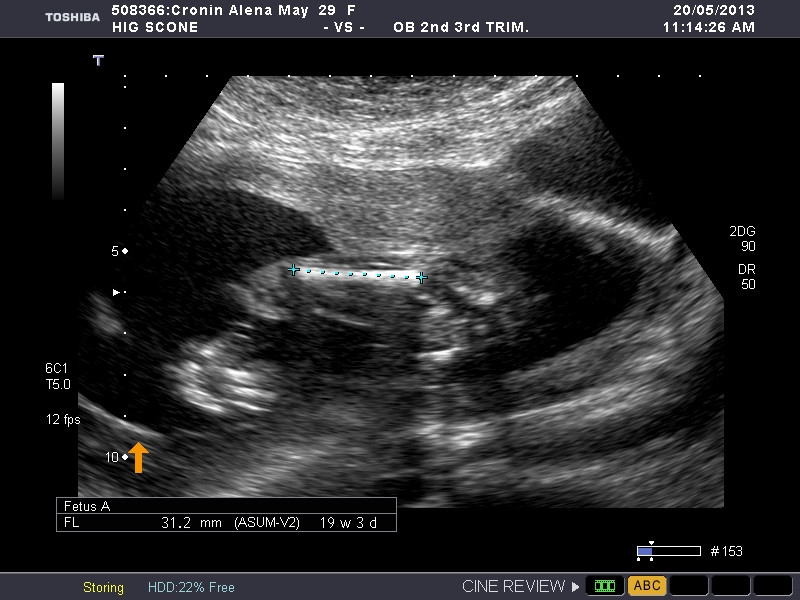

This is measureing femur any sex indicators?

Attachment 11372